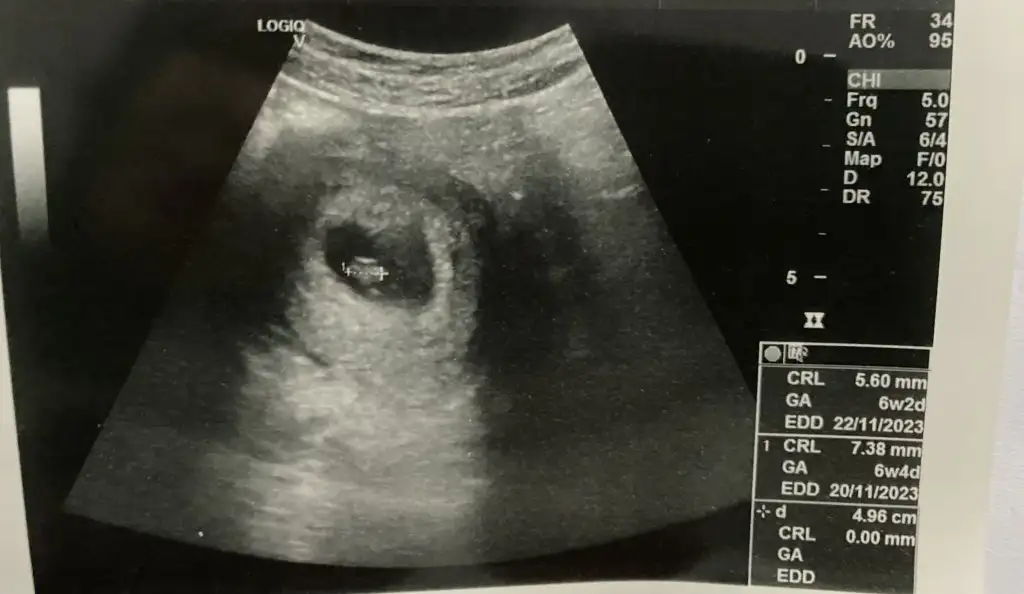

Parlak alan sağda bak burası plasenta. Yani teoriye göre kız. Ama biz eskiden direk bebeğe göre bakıyorduk, bunu daha yeni öğrendim.

Benimki ne oluyor o zaman